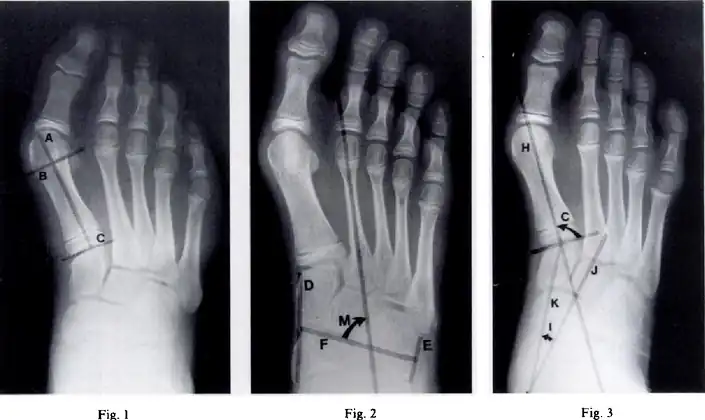

Metatarsus (primus) varus-Fig 1 - Length of the lateral cortex of the first metatarsal, Fig 2-metatarsus adductus angle measures the position of the lesser tarsus relative to the midfoot, Fig 3- the cuneiform angle -

A Sgarlato's angle of more than 15° indicates pigeon toe.[9]

Pigeon toe can be diagnosed by physical examination alone.[10] This can classify the deformity into "flexible", when the foot can be straightened by hand, or otherwise "nonflexible".[10] Still, X-rays are often done in the case of nonflexible pigeon toe.[10] On X-ray, the severity of the condition can be measured with a "metatarsus adductus angle", which is the angle between the directions of the metatarsal bones, as compared to the lesser tarsus (the cuneiforms, the cuboid and the navicular bone).[11] Many variants of this measurement exist, but Sgarlato's angle has been found to at least have favorable correlation with other measurements.[12] Sgarlato's angle is defined as the angle between:[9][13]

- A line through the longitudinal axis of the second metatarsal bone.

- The longitudinal axis of the lesser tarsal bones. For this purpose, one line is drawn between the lateral limits of the fourth tarsometatarsal joint and the calcaneocuboid joint, and another line is drawn between the medial limits of the talonavicular joint and the 1st tarsometatarsal joint. The transverse axis is defined as going through the middle of those lines, and hence the longitudinal axis is perpendicular to this axis.

This angle is normally up to 15°, and an increased angle indicates pigeon toe.[9] Yet, it becomes more difficult to infer the locations of the joints in younger children due to incomplete ossification of the bones, especially when younger than 3–4 years.